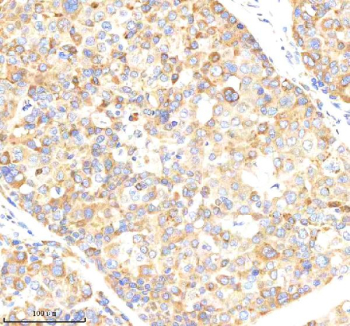

Immunohistochemical staining of NCLN using anti-NCLN antibody. NCLN was detected in a paraffin-embedded section of human liver cancer tissue. Heat mediated antigen retrieval was performed in EDTA buffer (pH 8.0, epitope retrieval solution). The tissue section was blocked with 10% goat serum. The tissue section was then incubated with 2 ug/ml rabbit anti-NCLN antibody overnight at 4oC. Peroxidase Conjugated Goat Anti-rabbit IgG was used as secondary antibody and incubated for 30 minutes at 37oC. The tissue section was developed using an HRP secondary and DAB substrate.